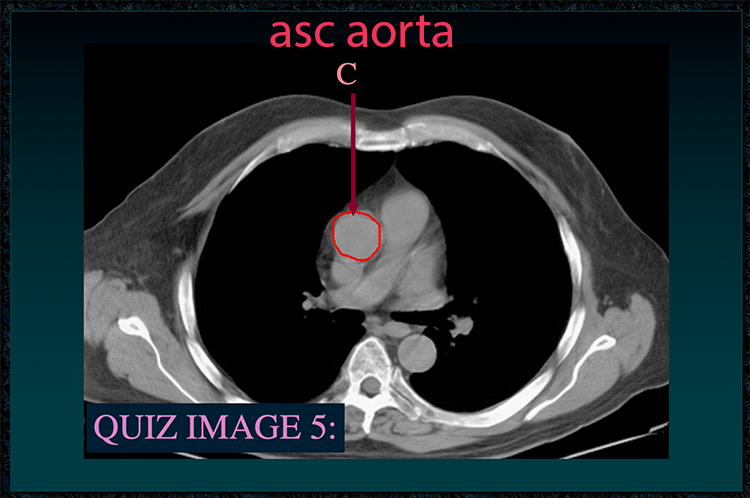

◂Chest Anatomy Review